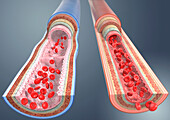

13435209 - Artery and vein, illustration

13443492 - Vein structure, illustration

13435208 - Artery and vein, illustration

13443491 - Vein structure, illustration

13443493 - Vein structure, illustration